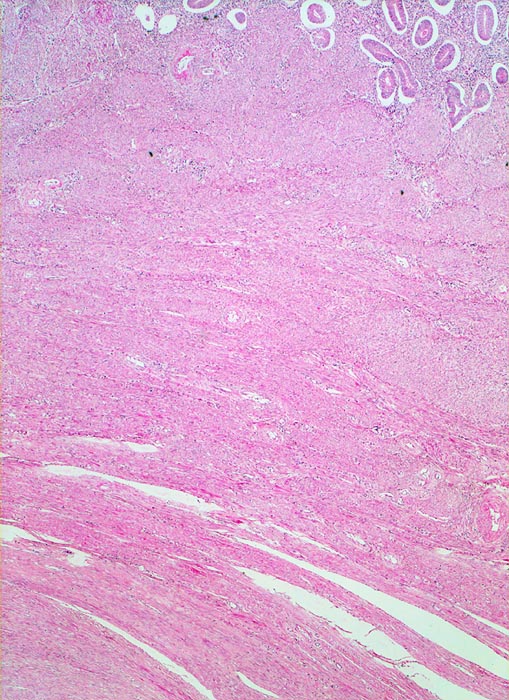

Myome imponieren makroskopisch typischerweise als runde, scharf begrenzte und nicht bekapselte Knoten. Die Schnittfläche ist weiss mit wirbliger Struktur. Mikroskopisch ist der Tumor aufgebaut aus Bündeln (=Faszikeln) spindelförmiger Zellen mit reichlich dunkel-eosinophilem Zytoplasma und an den Enden abgerundeten länglichen, zigarrenförmigen Kernen. Zell- und Fasergehalt sind sehr variabel. Degenerative Veränderungen wie Verkalkungen (> 4280), hyaline Nekrosen, Einblutungen, Homogenisierung des Kollagens, Ödem oder myxoide Degeneration und Zystenbildung (> 4279) kommen häufig vor. Manche gutartigen Leiomyome können ein einzelnes Malignitätskriterium aufweisen (vermehrte Mitosen, hohe Zellularität, deutliche Zellatypien oder Nekrosen). Falls mehr als eines dieser Kriterien vorhanden ist, handelt es sich differentialdiagnostisch um einen leiomyomatösen Tumor mit unsicherem Malignitätspotential (STUMP=Smooth Muscle Tumor of Uncertain Malignant Potential) oder um ein Leiomyosarkom. In seltenen Fällen lässt sich die Dignität nicht sicher bestimmen.

• Zwei scharf begrenzte Knoten im Myometrium bestehend aus Bündeln glatter Muskulatur.

• Variabler Anteil Fibrose (Kollagenfasern).

• Das Endometrium über dem Leiomyom ist druckatroph, das übrige Endometrium zeigt Proliferationszeichen.